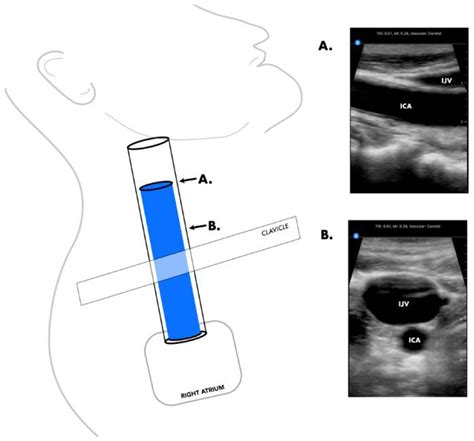

The carotid and jugular veins are both located in the neck, but they serve different purposes and have distinct anatomical features.

• Ultrasound: Ultrasound imaging can be used to visualize the jugular veins and detect any abnormalities, such as thrombosis or distention.